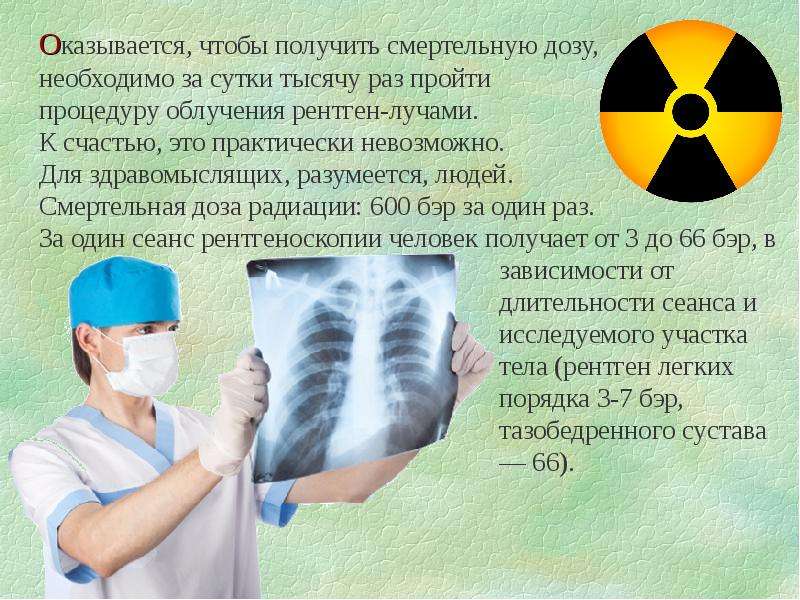

Изучение дозы излучения при рентгеновских исследованиях: визуализация